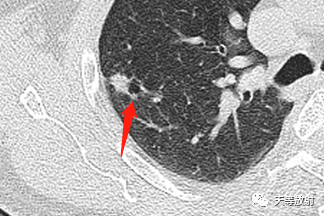

囊腔型腺癌CT病例解读。男性,64岁

2020.6.10

右肺上叶结节影,周围更小结节,形态不规则,胸膜面相对干净。